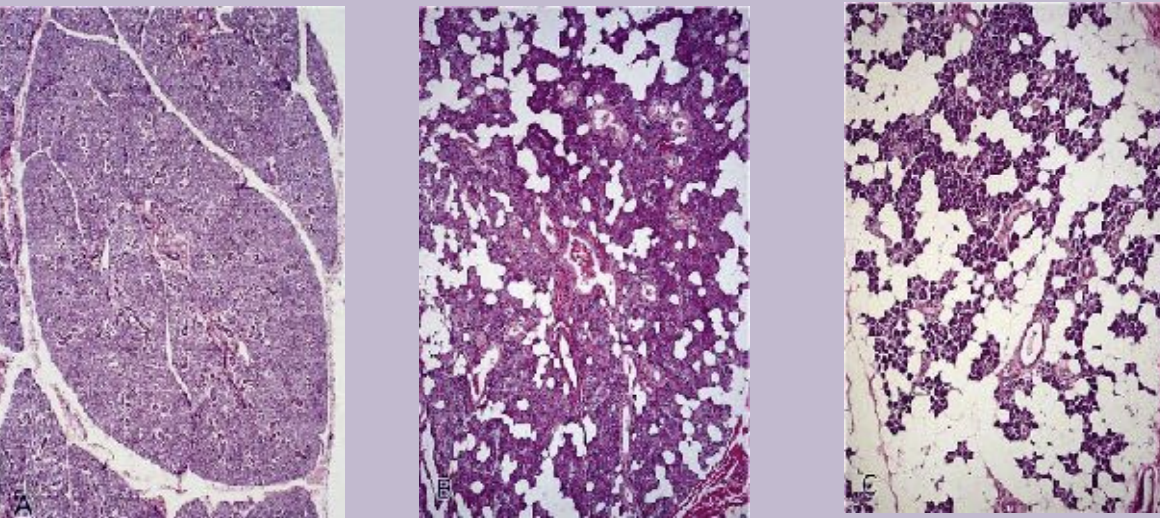

Histology – Maxillary Sinus (Key Points):

Lined by Schneiderian membrane (bilaminar):

Ciliated pseudostratified columnar epithelium (facing sinus)

Subepithelial layer with periosteum

Contains basal cells, non-ciliated columnar cells, goblet cells (mucus), and immune cells (lymphocytes, mast cells)

Ciliary beating moves mucus toward nasal cavity

Mucus blanket is essential for ciliary function